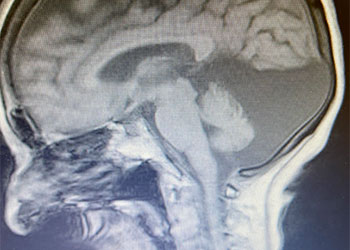

B) Pre-operative, sagittal post-contrast MRI

Fig 1. B) Pre-operative, sagittal post-contrast MRI.